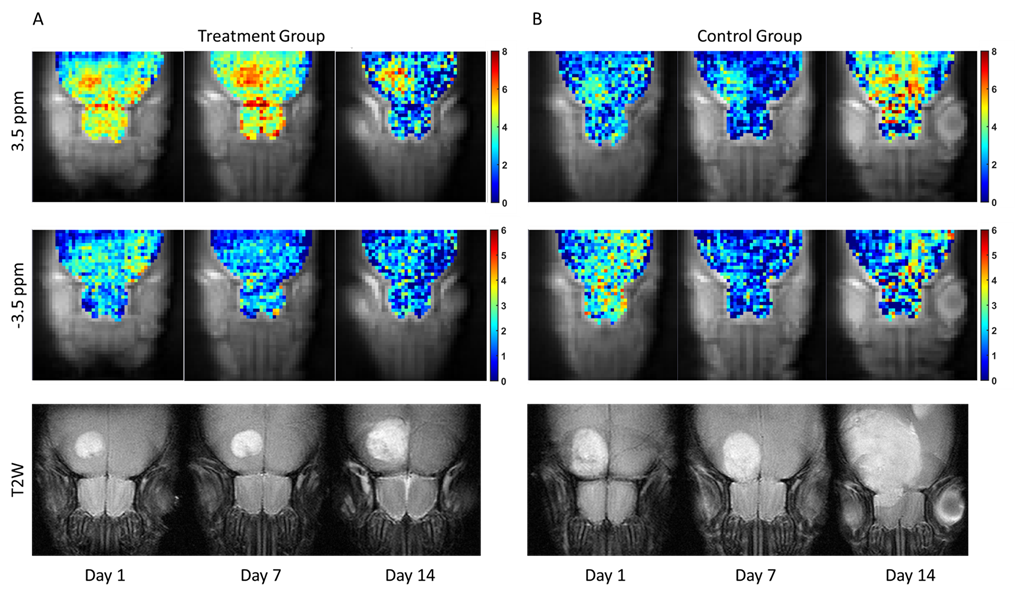

本研究旨在通过多种化学交换饱和转移(CEST)对比,监测经鼻给药至脑肿瘤的治疗方法,并评估治疗效果。研究重点在于利用CEST技术监测药物在脑肿瘤中的传递和治疗效果。研究者使用了基于脂质体的药物递送系统,通过经鼻途径将药物传递至脑部,并使用3T磁共振成像(MRI)进行CEST成像,以监测药物递送和肿瘤反应。实验结果显示,治疗组的肿瘤大小显著小于对照组,表明了治疗的疗效。CEST对比在3.5ppm处的变化与肿瘤区域的治疗效果相关,而4.3ppm和-3.5ppm处的CEST对比变化则指示了脂质体药物的递送效率和累积分布。研究讨论了CEST成像在监测药物递送和评估治疗效果方面的潜力,以及如何通过CEST对比的变化来评估药物在脑肿瘤中的累积和分布。结论强调了CEST成像作为一种无创监测工具在脑肿瘤治疗中的潜力,以及其在临床应用中的潜在价值。

治疗组和对照组(n=2)的体内肿瘤监测。(A) 治疗组 3.5 ppm、-3.5 ppm 处的 CEST 图和 T2图像 (B) 对照组 3.5 ppm、-3.5 ppm 处的 CEST 图和 T2图像